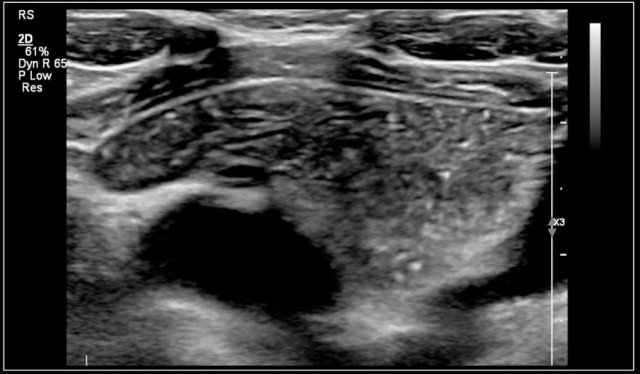

Here an ultrasound of a typical lymphangioma.

MRI was performed because the extension of the lesion was not clear.

Here the T2-weighted image of the same patient.

On T1-weighted images the content has a variable signal intensity, depending on its protein or blood content.

It generally has a high signal intensity on T2-weighted images.

Contrast enhanced T1 can show enhancement of the wall.